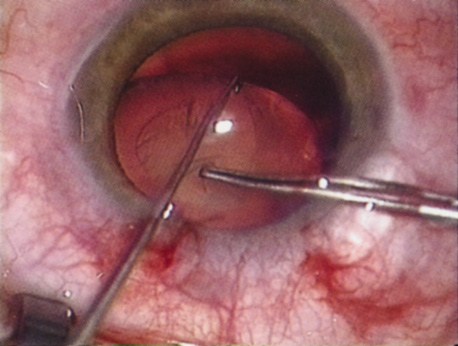

ANTERIOR CAPSULOTOMY

One of the most beneficial techniques developed over the last decade is capsulorrhexis. A continuous curvilinear anterior capsular opening helps prevent intraoperative and postoperative complications. With capsulorrhexis, mechanical strength of the capsular opening is superior to that in a can-opener capsulotomy; thus, a tear to the posterior capsule with subsequent vitreous loss is much less likely.96 Capsulorrhexis allows for nuclear manipulation with less risk of posterior capsule rupture. Cortex removal is made easier as well, because it becomes easier to differentiate cortical material from anterior capsule. Should a posterior capsular tear occur, sulcus fixation is more likely attainable with the presence of a clearly visible residual anterior capsular rim. Placement of both IOL haptics into the capsular bag is more certain with capsulorrhexis because the surgeon can more easily visualize the haptics gliding beneath the anterior capsular rim.

Capsulorrhexis can be performed with a cystitome, capsulorrhexis forceps, or combination-type instruments. Regardless of which instrument is used, several principles can help the surgeon successfully complete capsulorrhexis. It is important to maintain the anterior chamber, because making the chamber shallow increases tension on the zonules and causes the tear to run peripherally. The authors recommend the use of a viscoelastic agent for maintaining chamber depth and, of course, for endothelial protection. Therefore, if the tear begins to run peripherally, the surgeon should redeepen the anterior chamber before attempting to redirect the tear. Additionally, folding the capsule margin can aid the surgeon in redirecting the tear more accurately (Fig. 10).

Fig. 10. The capsulorrhexis tear is more easily redirected by folding the capsule over, in advance of the tear.